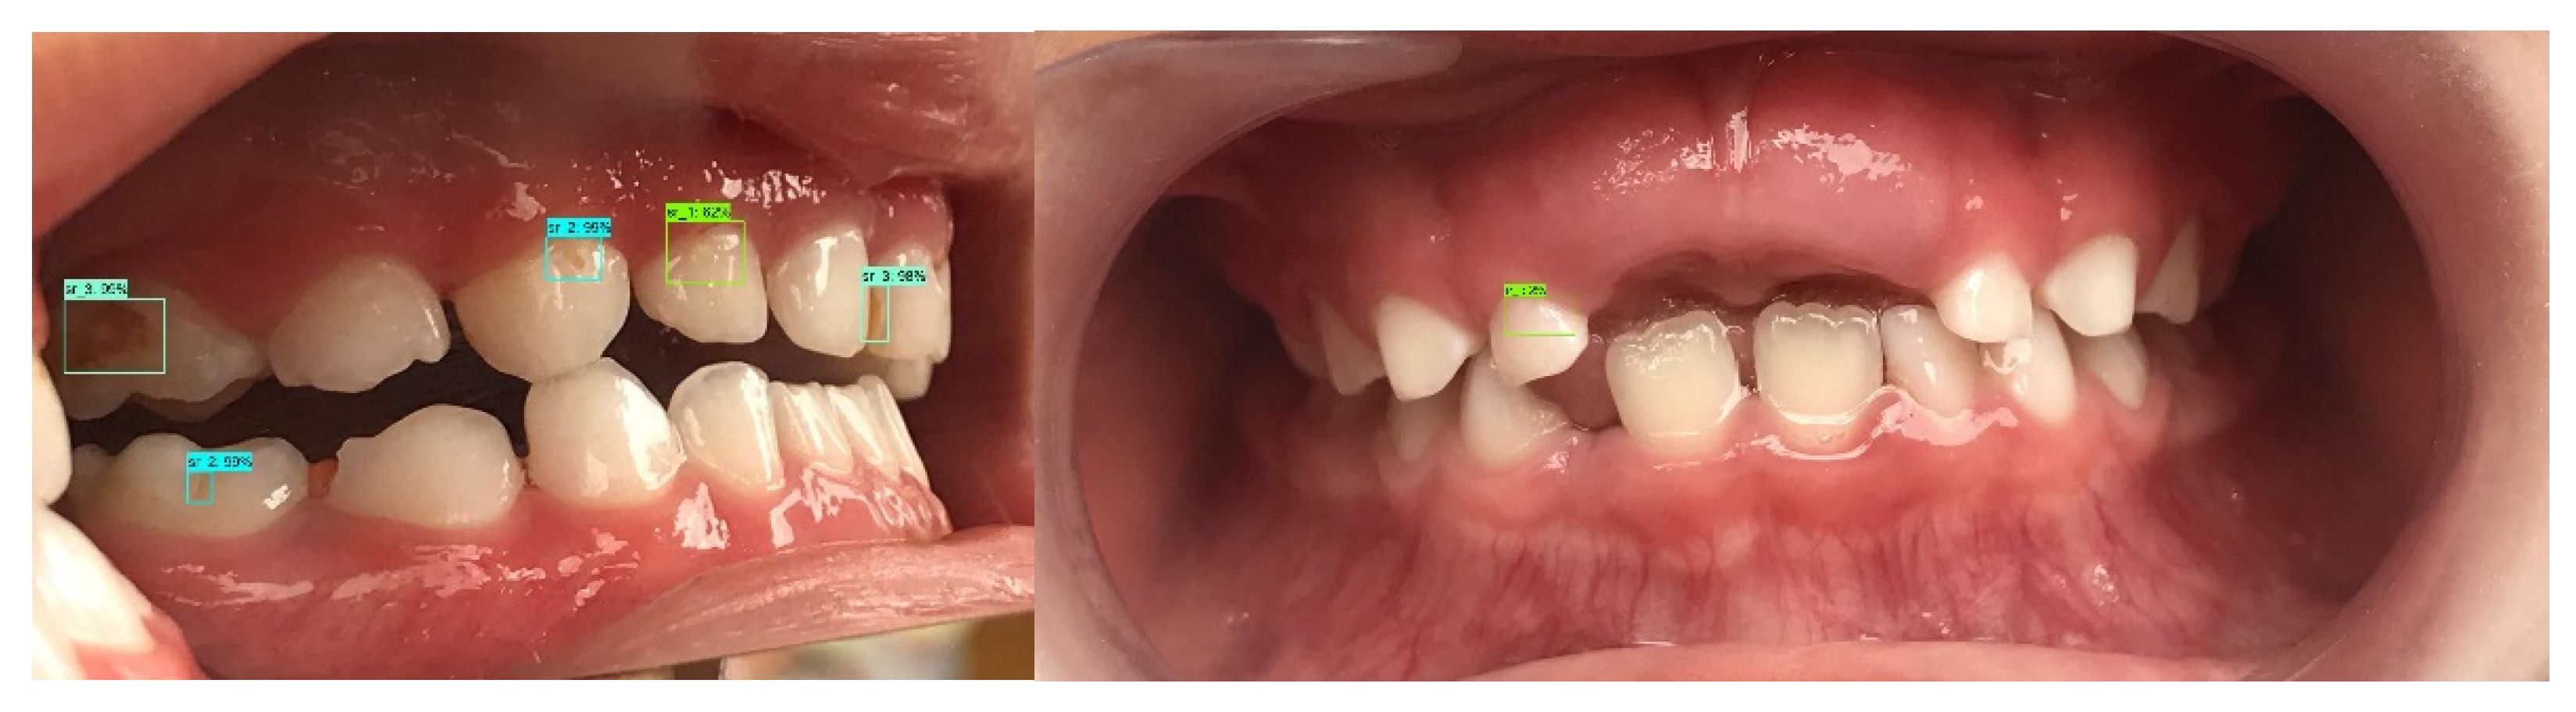

Deep Learning Application in Dental Caries Detection Using Intraoral Photos Taken by Smartphones

2. Materials and Methods

2.1. Photographic Images

2.2. Reference Standard and Labeling Dataset